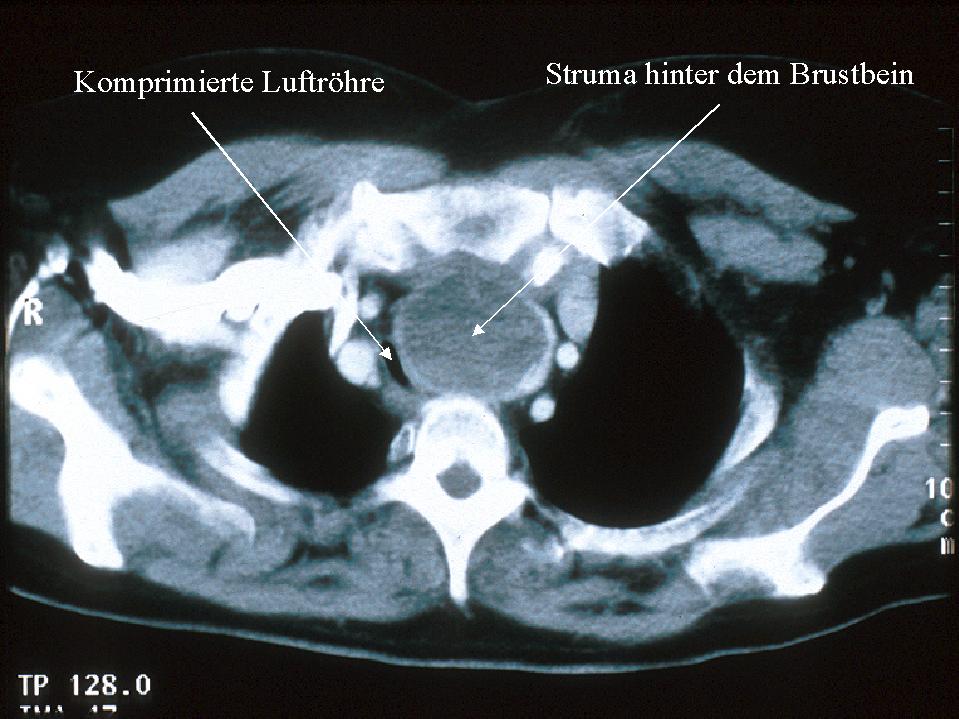

Computertomographie

oder Kernspintomographie

oder Kernspintomographie des Halses und des

Thorax bei sehr großen, hinter das Brustbein

reichenden Strumen sowie bei ausgedehnten

bösartigen Schilddrüsenerkrankungen (CT

immer ohne Kontrastmittel !!)